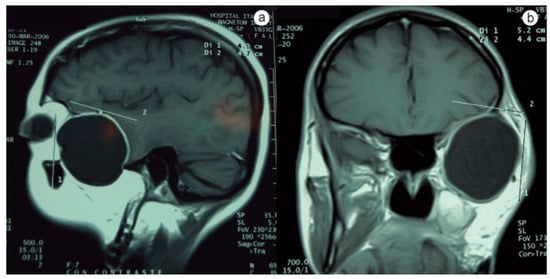

:Case History